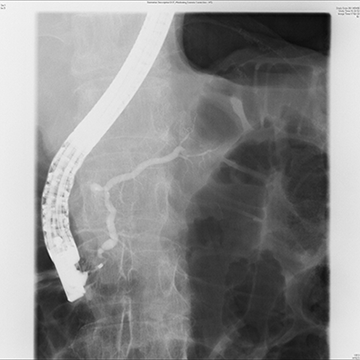

大腸腫瘍に対する内視鏡的粘膜下層剥離術(ESD)